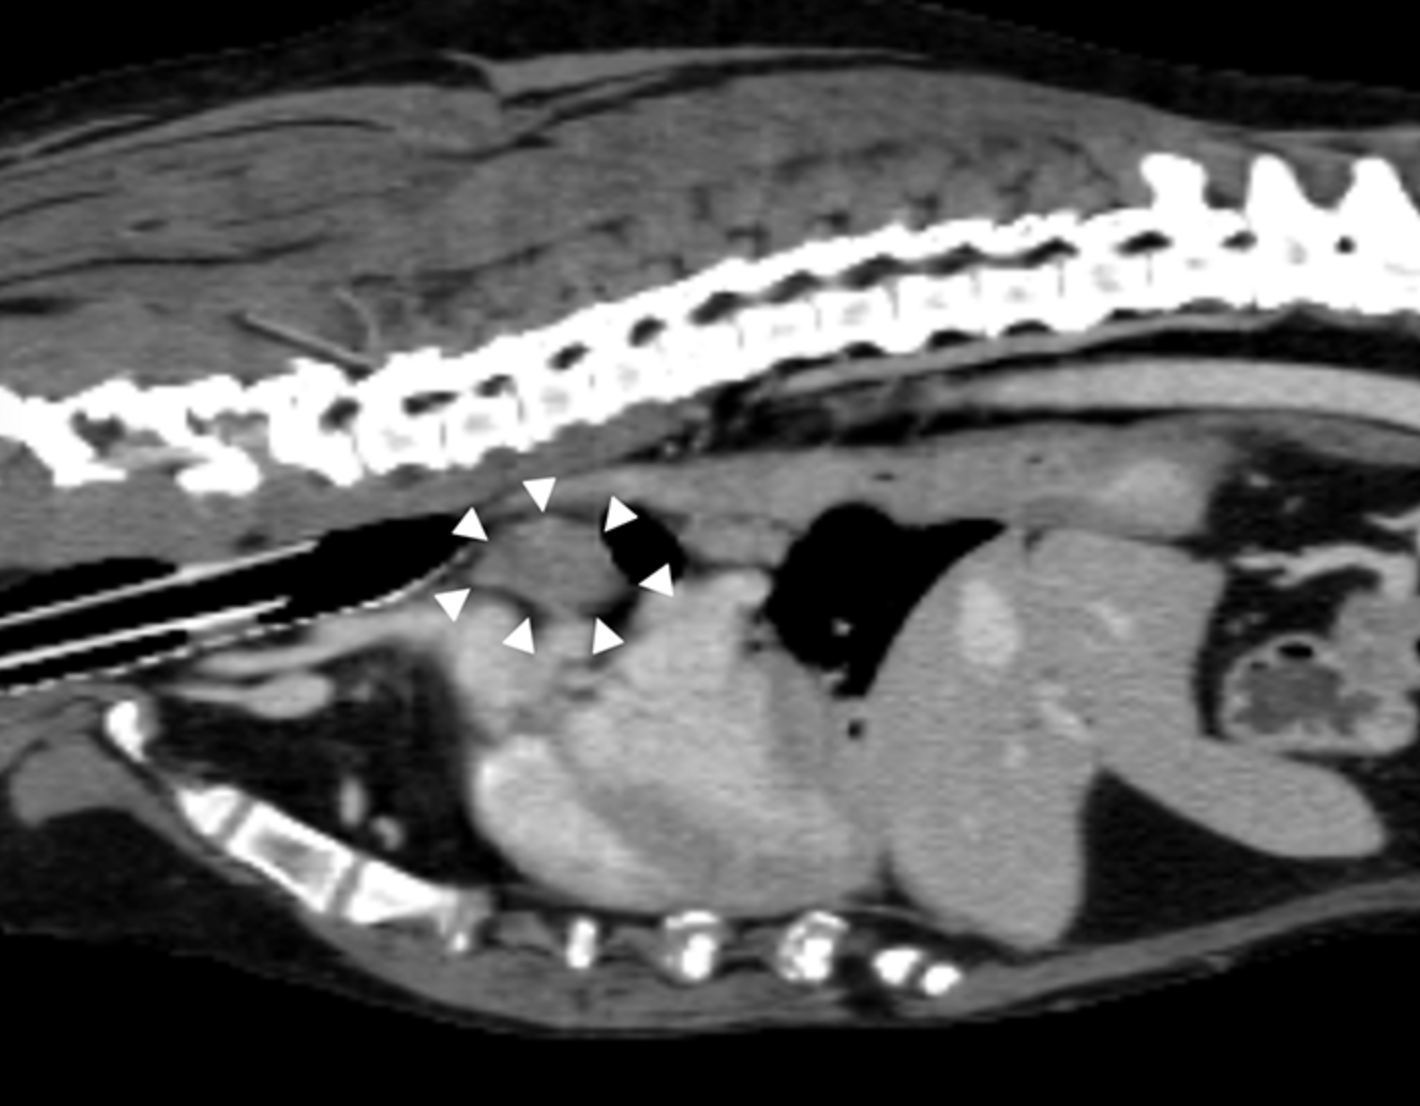

La metástasis en los ganglios linfáticos se identificó mediante histopatología quirúrgica en algunos perros que tenían ganglios linfáticos radiológicamente normales según las imágenes de TC. Esto resalta la importancia de la extirpación quirúrgica de los ganglios linfáticos cuando sea posible, a pesar de que la anatomía es ocasionalmente desafiante e independientemente de los hallazgos de las imágenes preoperatorias. Se justifica la investigación adicional sobre el impacto a largo plazo de la metástasis en los ganglios linfáticos en perros con tumores pulmonares primarios.